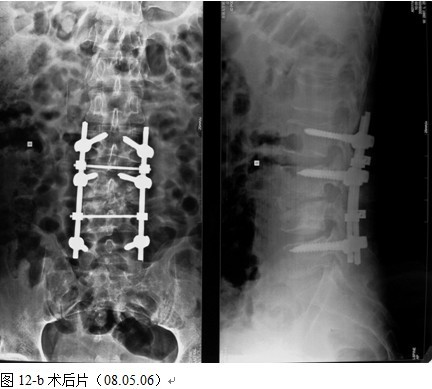

本组手术用时间3~4h , 平均3.5h 。术中出血300~500ml , 平均约350ml 。术后症状完全缓解,无神经功能障碍加重等并发症,1例营养差的老年患者伤口出现窦道,1例因肝功能差,术后未口服抗痨药,伤口出现窦道,经换药后二期愈合,其余病例伤口均一期愈合。马尾神经受损的患者术后基本恢复正常。术后一周后凸角平均 5.4°后凸畸形平均矫正90%以上, 最终后凸角平均8.3°,后凸角度平均丢失4.2°。随访3个月有87%(40/46)有骨痂形成,6个月91.3%(42/46)明显骨性愈合(见图),其余4例9-12个月内愈合,随访时间3-32个月,平均11个月,46例患者中2例在术后2个月和3个月时背部形成脓肿,换药后治愈。2例出院1月后并发结核性脑膜炎,治疗后好转。1例因椎弓根钉偏外,刺激神经根,5个月后从侧方脱出,疼痛加重,因前后路植骨完全愈合,取出后症状完全缓解。